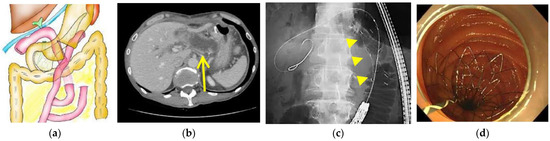

2.3. Endoscopic Procedure